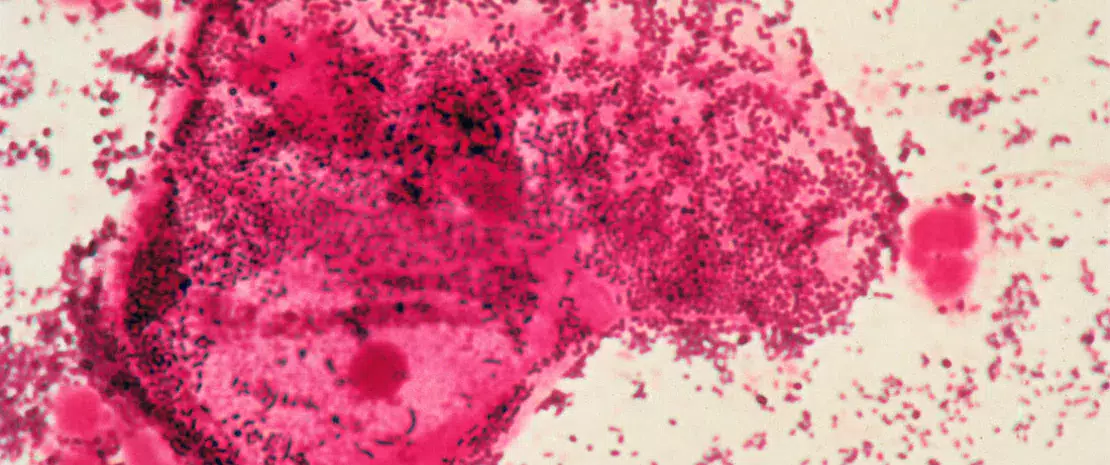

La  (sidenote: Vaginose bactérienne La vaginose bactérienne (VB) est un type d'inflammation vaginale causée par un déséquilibre des espèces de bactéries qui sont normalement présentes dans le vagin. ) (VB) est souvent un signe caractéristique d'un déséquilibre dans le microbiote vaginal, une maladie qui pourrait résulter de la transmission sexuelle de bactéries. Bien que la communauté scientifique reconnaisse l'éventualité d'une telle transmission, la compréhension définitive nous échappe encore. Des chercheurs américains de l'University of Maryland School of Medicine ont étudié comment des souches bactériennes similaires se comportaient entre des partenaires sexuels et au sein de réseaux sexuels plus vastes, afin de mieux comprendre la transmission sexuelle et d'améliorer la prise en charge de la maladie pour les deux partenaires. 1

Les chercheurs ont recueilli et analysé des échantillons de prélèvements vaginaux et péniens à l'aide du séquençage métagénomique global, une méthode permettant de lire l'intégralité des séquences ADN présentes dans un échantillon, afin d'analyser en détail la communauté microbienne. Ils ont utilisé des outils comme inStrain pour évaluer la « concordance des souches », ou le degré de similitudes génétiques, entre les bactéries trouvées chez différents individus, en vue d'identifier si les souches sont partagées par contact sexuel.

Sur 54 participants, l'étude a identifié 115 cas de recoupements de souches bactériennes parmi 25 espèces. Étonnamment, Lactobacillus iners a été transmis chez 6 % des participantes, ce qui suggère des voies de transmission directe lors d'interactions entre personnes de même sexe. Des comparaisons directes ont révélé un taux de partage de souches bactériennes bien supérieur en cas de contacts sexuels par rapport à l'absence de contact.